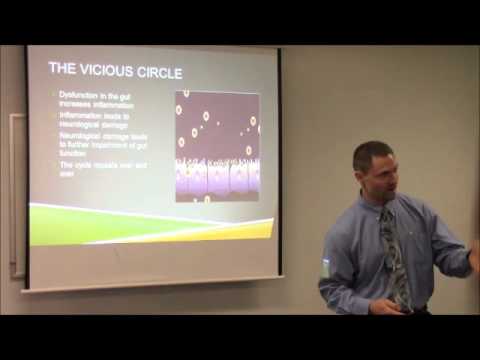

Dr. Arland Hill, DC, MPH, DACBN discusses the role of autoimmunity in autism. Topics reviewed includ [...]